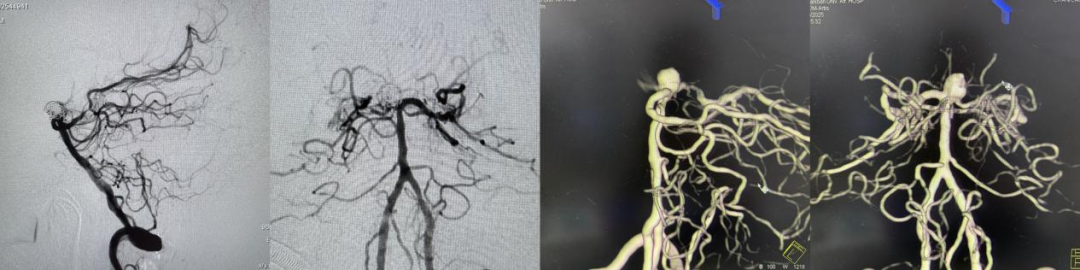

图1:左侧颈内动脉后交通段动脉瘤支架辅助栓塞术前后造影